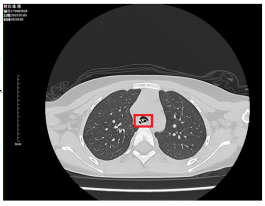

在家长的绝对信任和支持下,医疗团队决定在静脉镇静的状态下为小女孩进行CT检查。几分钟后,放射科副主任医师苟代文传来了令人揪心的消息:小女孩气管内存在异物!这一发现立即让整个医疗团队进入了高度紧张状态,因为他们深知,时间就是生命,任何延误都可能带来不可挽回的后果。